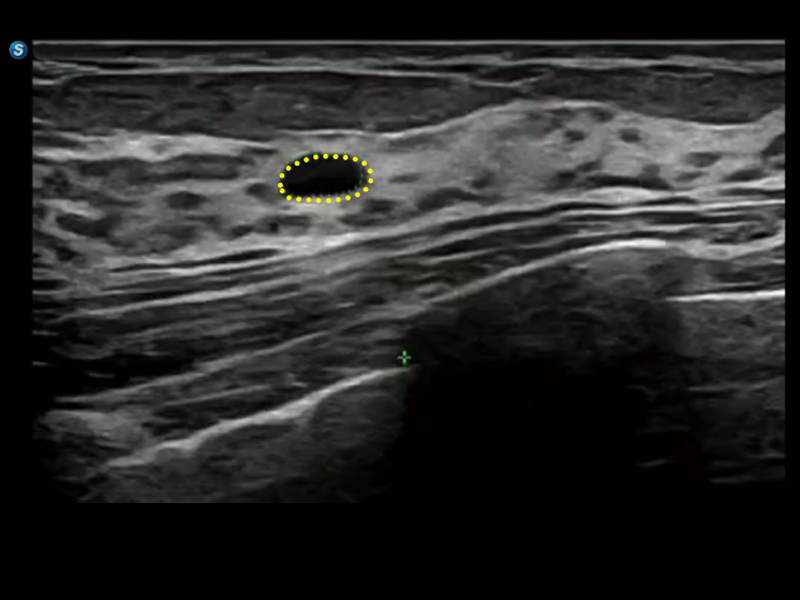

探头内置感知传感器,支持拿起探头即唤醒,快速开启扫查。同时支持多档灵敏度可调,用户可随心配置,调节唤醒灵敏度